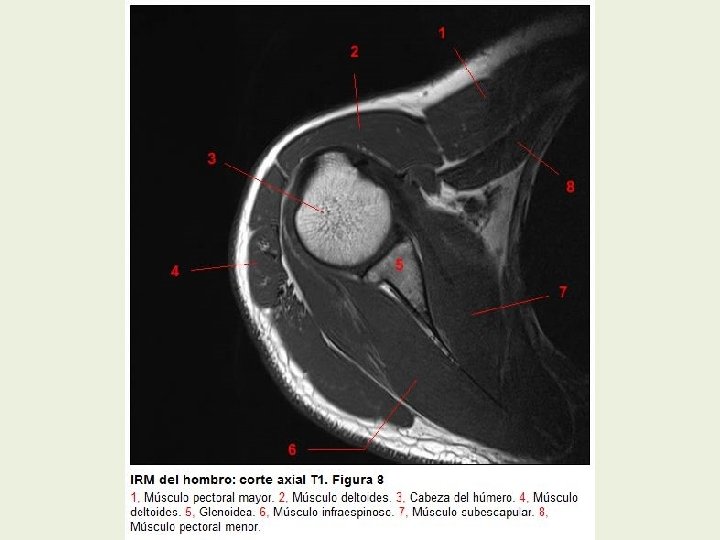

Hombro Cortes axiales RMN